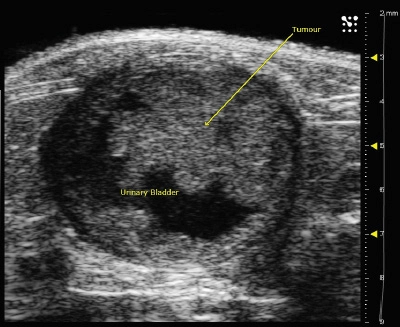

Cancer Imaging

Detect pre-palpable tumors earlier and monitor growth using high resolution, all at high throughput.